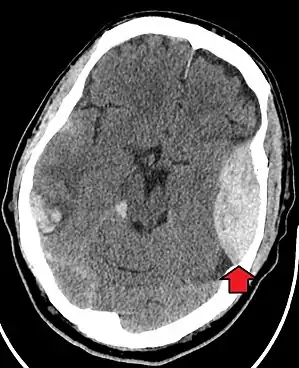

| Epidural hematoma as seen on a CT scan with overlying skull fracture. Note the biconvex shaped collection of blood. There is also bruising with bleeding on the opposite side of the brain. | |

Epidural hematomas usually appear convex in shape because their expansion stops at the skull's sutures, where the dura mater is tightly attached to the skull. Thus, they expand inward toward the brain rather than along the inside of the skull, as occurs in subdural hematomas. Most people also have a skull fracture.[3]